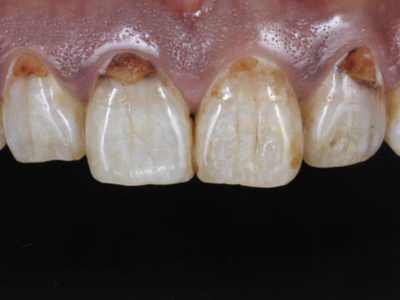

酸蚀症牙齿缺损不平整图

酸蚀症患者的牙齿会发生缺损,轻度时仅表现为牙齿尖端凹凸不平,有少量骨质缺失,缺损处有黄褐色至红褐色斑点,该病可能是长期接触外源性酸性物质而致病。